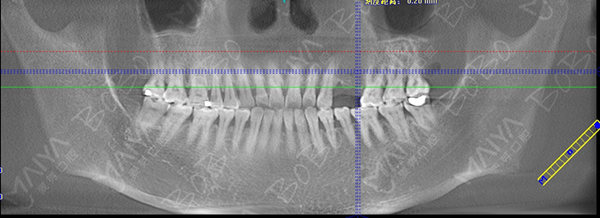

赵女士种牙前口腔全景ct

由于赵女士长期牙缺失,牙槽骨已经出现萎缩吸收,导致两边邻牙倾斜,因此她的牙缺失间隙在动态变小,牙齿的间隙不够种植两颗牙的位置,但是种一颗牙又显得空间有点偏大,最终专家团经综合考虑,采用麦芽MAC数字化种植技术,数字化精确导航种植,采取了种植一颗连冠修复的方式,只需一颗种植钉就可以达到修复两颗牙齿的目的,仅仅不到一个小时就帮赵女士种上了牙齿。